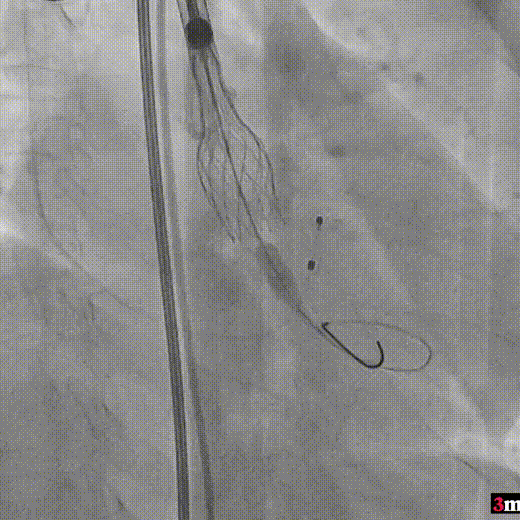

完全释放后造影疑似左冠狭窄

IVUS探查左冠开口狭窄60%

放置开窗支架

球囊后扩支架

假体瓣膜形态良好,无明显瓣周漏

术后测量跨瓣压差仅为1mmHg